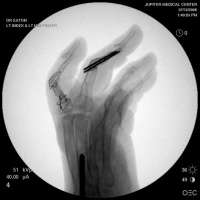

Xrays show radiocarpal collapse, proximal migration of the proximal phalanges, flail PIP joints and loss of the proximal half of the dorsal cortex of the proximal phalanges.

Below are xrays after the first set of reconstructions.

For the second stage of her reconstruction, the index proximal phalanx did not have adequate dorsal cortex to support an implant arthroplasty, and bone graft from the metacarpal head was used to reconstruct this.